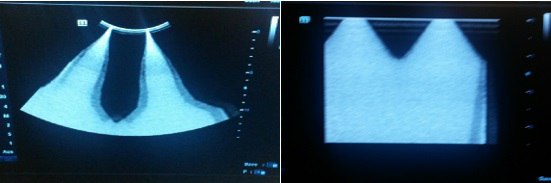

⚠️ Проблема: С течением времени эхо-изображение на DC-70 становится слабее, после чего в течение нескольких секунд исчезает. Меню отображается нормально. Переключение на другой датчик вызовет то же самое явление.

💡 Причина: Схема ЦАП на PHV плате вышла из строя, в результате чего напряжение PHV отклонилось от нормы. После замены PHV платы проблема была решена.

1.png

✅ Решение: Заменить PHV плату.